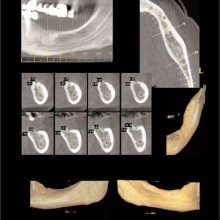

IMPLANTS: Implants that are used to replace missing teeth, for anchorage to mobilize teeth, or dental segments and, in some cases, can be restored to optimize function and esthetics. Implants need to be located where they will have the best chance for success. Prosthetic, anatomic, and biomechanical requirements independently or in combinations are key considerations to be resolved. Three-dimensional imaging techniques can play a significant role revealing the anatomic considerations and linking them to the prosthetic and biomechanical treatment options (Figures 5, 6).

IMPACTIONS: Imaging can contribute greatly to localizing impacted teeth, identifying associated pathology, assist planning surgical access, and assist with designing the traction mechanics for moving the impacted tooth into the dental arch and occlusion (Figures 9, 10).

The anatomy sets some of the boundary conditions for tooth position. The identification and visualization of these boundary conditions can be performed by applying volumetric CT during initial workup. There are clinical instances when tooth movement is prevented or diminished because of anatomic boundaries, such as cortical margins, adjacent teeth, and dense bone. In addition, expansion of the dental arch form or tooth torque may be limited or confined by the labial and buccal cortical margins of the alveolar bone. These boundaries are difficult to visualize without the aid of cross sectional or three-dimensional imaging techniques (Figure 9).